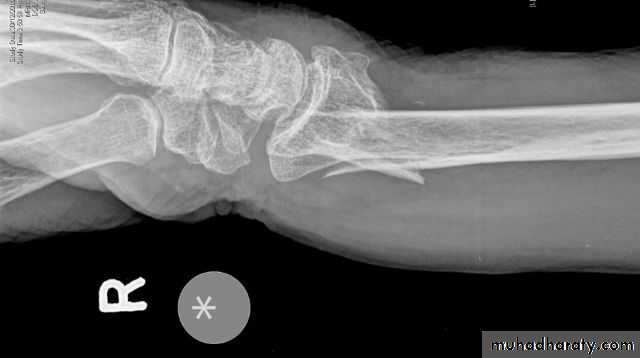

We can recognize this fracture (as Colles did long before radiography was invented) by the ‘dinner-fork’ deformity, with prominence on the back of the wrist and a depression infront.In patients with less deformity there may only be local tenderness,swelling and pain on wrist movements.

There is a transverse fracture of the radius at the corticocancellous junction, and often the ulnar styloid process is broken off. The radial fragment is impacted into radial and backward tilt. Sometimes there is an intra-articular fracture; sometimes it is severely comminuted.TREATMENT